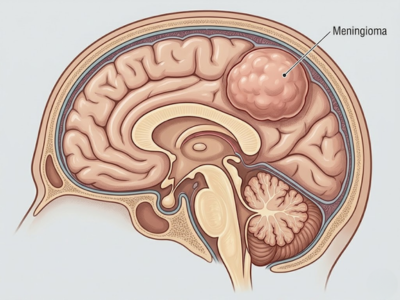

Meningiomas

Tumors that form in the meninges, the protective layers around the brain.